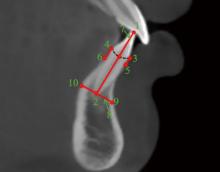

Uribe F, Padala S, Allareddy V, et al. Cone-beam computed tomography evaluation of alveolar ridge width and height changes after orthodontic space opening in patients with congenitally missing maxillary lateral incisors[J]. Am J Orthod Dentofacial Orthop, 2013, 144(6): 848-859.

Dos Santos PBD, Herrera Sanches FS, Ferreira MC, et al. Movement of mandibular molar into edentulous alveolar ridge: A cone-beam computed tomography study[J]. Am J Orthod Dentofacial Orthop, 2017, 151(5): 907-913.

Lu M, Li WX, Wang YQ, et al. The orthodontic implant site-switching technique: A preliminary study in dogs[J]. Head Face Med, 2023, 19(1): 29.